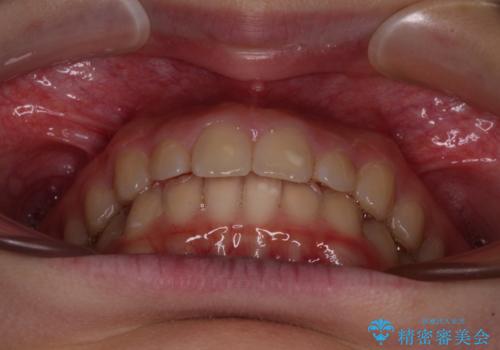

- ヨーロッパにてインビザライン矯正を始めたものの、日本に転居することになり、治療の継続を希望して来院された患者様です。

治療計画に無理がなく、現地担当医と速やかに連絡が取れるとのことで、インビザライン社での転医手続きを行い、継続して治療を行うこととしました。

舌の突出癖により、上下前歯が非接触となっていたため、トレーニングを徹底的に指導し、安定した咬み合わせにより終了させることができました。